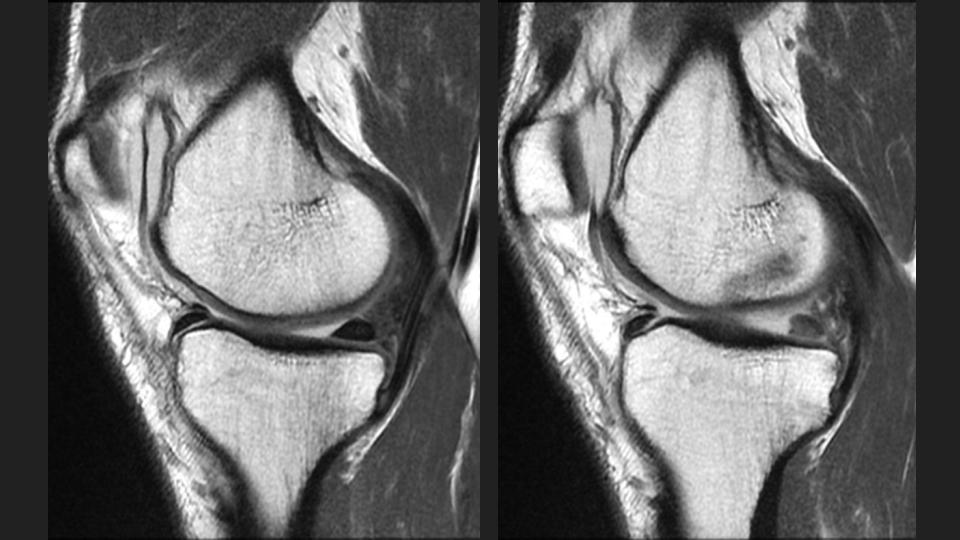

49M runner with pain since twisting injury during marathon 1 year ago

There is a radial tear / avulsion of the posterior horn medial meniscal root (red arrow), which is likely related to the running injury 1 year ago. There is stress related marrow edema, but it is not localized deep to the root anchor. There is 3mm (borderline) extrusion of the medial meniscal body (white arrow), but there is surprising preservation of the medial compartment articular cartilage. Meniscal root tear is known to predispose to medial compartment cartilage loss, which is often rapid. Hes obviously symptomatic and has stress related marrow edema, but why hasnt he developed medial compartment OA?

posterior horn of medial meniscus ( RID2776 )